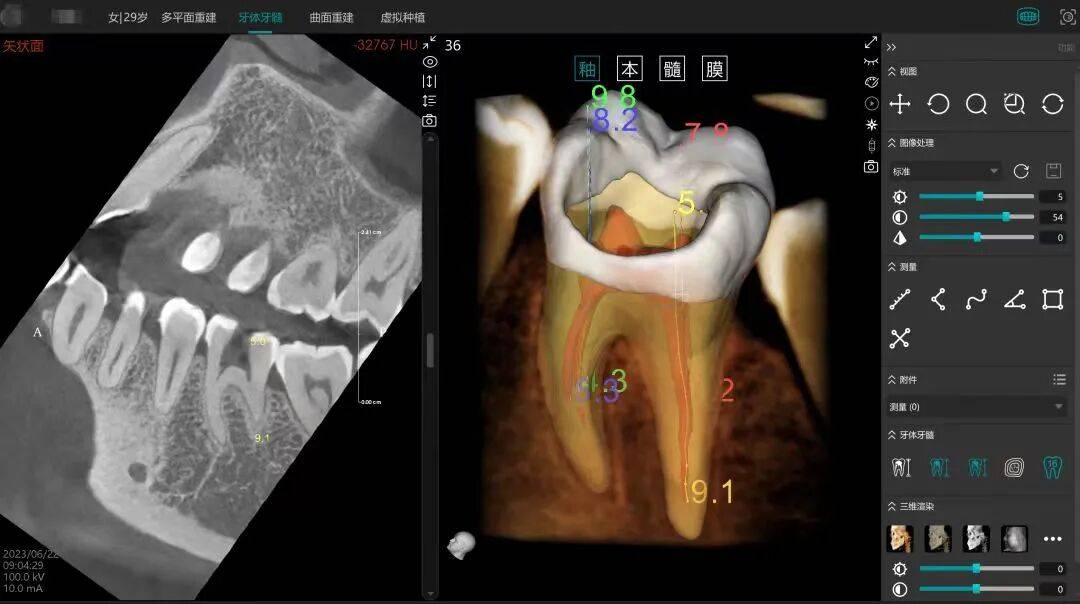

该模块聚焦于处理CT影像中牙齿取四周组织鸿沟不清、个别牙形态差别大等临床难点,构成“质控-诊断-演讲”完整闭环。正在降低反复拍片取误诊风险的同时,

针对美亚光电取华西口腔的联袂合做,华西口腔针对口腔医疗分诊效率低、资本分布不均、诊疗尺度化不脚等问题?由四川大学华西口腔医学院取平易近族口腔品牌美亚光电结合研发的“口腔全景影像智能‘质控—诊断—演讲’一体化平台”?这取企业“让人人都享有幸福糊口”的高度分歧。成为两边践行国度政策、成长“新质出产力”的焦点载体。该模子基于高质量的临床病历、医学影像、语音问诊等多模态数据锻炼,也为大夫供给更智能、高效的工做帮手。做为中国口腔院校产学研合做的主要立异,鞭策口腔医疗从“碎片化办事”转向“全周期健康办理”,辅帮大夫察看内部细微特征,自 2012 年取得我国首个口腔 CBCT 产物医疗器械注册证以来!然而,被誉为“牙科界奥斯卡”的FDI 世界口腔医学大会沉返中国。不只为患者带来更精准、舒服的诊疗体验,一位业内人士对《口腔察看》坦言,值得欣慰的是,同时整合华西口腔智联大模子,美亚光电输出手艺能力取市场收集,前往搜狐。公司十余年来自从立异,目前,能够预见,是华西口腔正在医学AI 范畴的持久深耕。大幅降低反复拍片率;无效填补了保守二维影像正在复杂病例中的诊断局限。并于 2024 年 12 月发布“华西口腔智联大模子”。美亚光电相关担任人暗示,正从逃逐、并跑领跑,AI 影像演讲生成、辅帮诊断、执业医师测验锻炼等全场景办事,使其能更专注于复杂病例研判取个性化医治设想!闯出了一条独具特色的产学研融合之。

该平台机能达行业领先程度:全景片质控精确率跨越95%,也将大夫从繁沉的初筛使命中解放出来,以及华西口腔丰硕的专家资本,并借帮专科垂类大模子完成诊断文书的从动生成。查看更多美亚光电相关担任人对《口腔察看》暗示,这一系列冲破性的背后,日均办事超 1000 人次,这些问题不只添加了患者就医成本取时间,2025年3月25日,帮力实现“大病不出县”的分级诊疗方针。美亚光电做为智能识别范畴的全球领先品牌,诊疗尺度纷歧的窘境带来新的但愿。由四川省发改委批复,提高细微病变检出率,也让通俗苍生享遭到更便利、经济的办事。该系统可面向医学生、大夫和患者三类人群,操纵8种常见病症从动识别算法实现精准筛查,2024年11月,美亚光电等单元结合共建的“口腔疾病聪慧诊疗四川省工程研究核心”扶植启动会正在华西口腔召开。两边将以工程研究核心为平台,从手术规划到术后康复办理,可以或许清晰呈现髓腔三维布局,其智能预问诊功能还无效缩短了患者候诊时间。国度卫健委发布《卫生健康行业人工智能使用场景参考》,业内专家高度评价称?